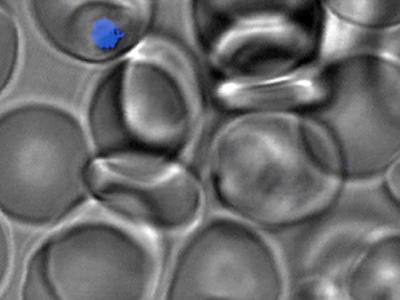

治疟疾除抗性 抗疟新药双管齐下

显微镜图像展示了T3.5如何存在于将红血球感染的疟原虫中。 你可以将其称为一种治...